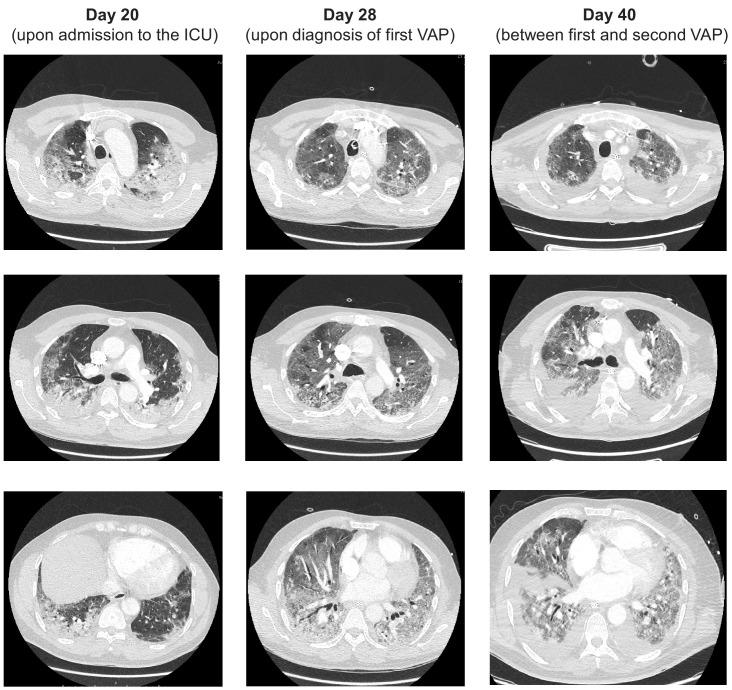

Here, we describe the case of a COVID-19 patient who developed recurring ventilator-associated pneumonia caused by that acquired increasing levels of antimicrobial resistance (AMR) in response to treatment. Metagenomic analysis revealed the AMR genotype, while immunological analysis revealed massive and escalating levels of T-cell activation. These were both SARS-CoV-2 and specific, and bystander activated, which may have contributed to this patient's persistent symptoms and radiological changes.

在这里,我们描述了一例 COVID-19 患者的情况,该患者因治疗而导致获得性抗菌药物耐药性(AMR)不断增加,从而反复发生呼吸机相关性肺炎。宏基因组分析揭示了 AMR 基因型,而免疫分析揭示了大量和不断升级的 T 细胞激活。这些都是 SARS-CoV-2 和 的特异性和旁观者激活的,这可能导致了该患者持续的症状和影像学改变。